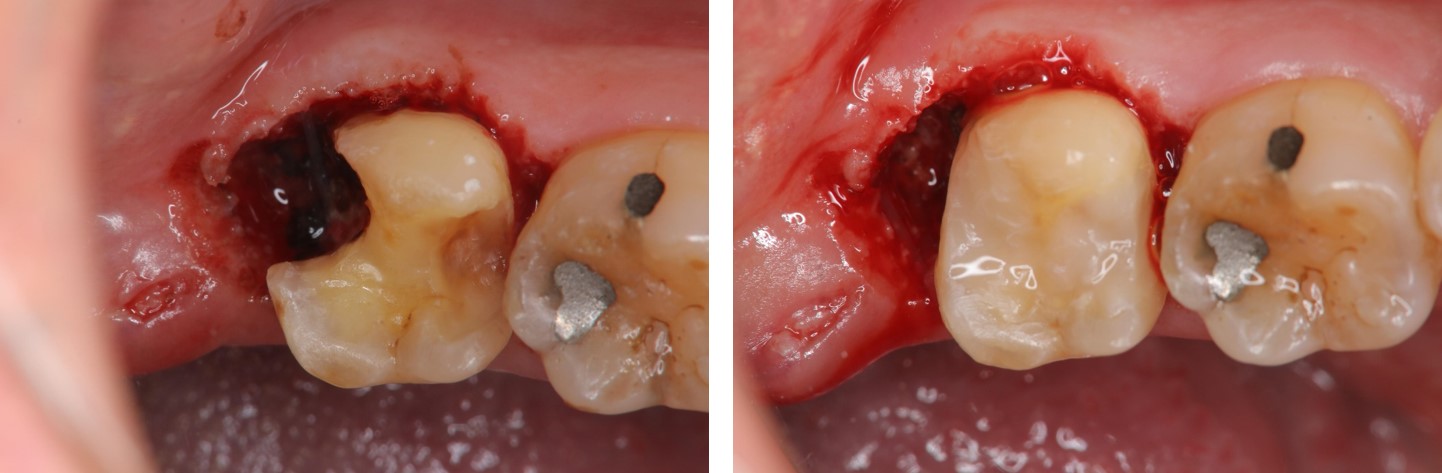

MTA覆髓及水雷射牙冠增長手術